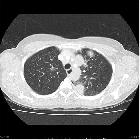

CT

Described CT features include:

- nodules or masses: variable size but typically ~2-4 cm

- multiple in 75%

- no zonal predilection

- irregularly margined

- cavitation with irregular / thick-walled cavity margins seen in ~40-50% of cases

- cavitation may be seen in 25% of nodules >2 cm

- can have a peribronchovascular or subpleural distribution

- waxing and waning even without treatment

- micronodules: centrilobular tree in bud nodules are usually related to bronchiolar wall involvement or retained blood products in the distal airways, seen in about 10% of cases

- air space consolidation

- peripheral wedge-shaped opacities (due to pulmonary infarcts)

- ground glass changes

- frequently as a consequence of hemorrhages

- may relate to nodules or regions of consolidation

- may be the main abnormality